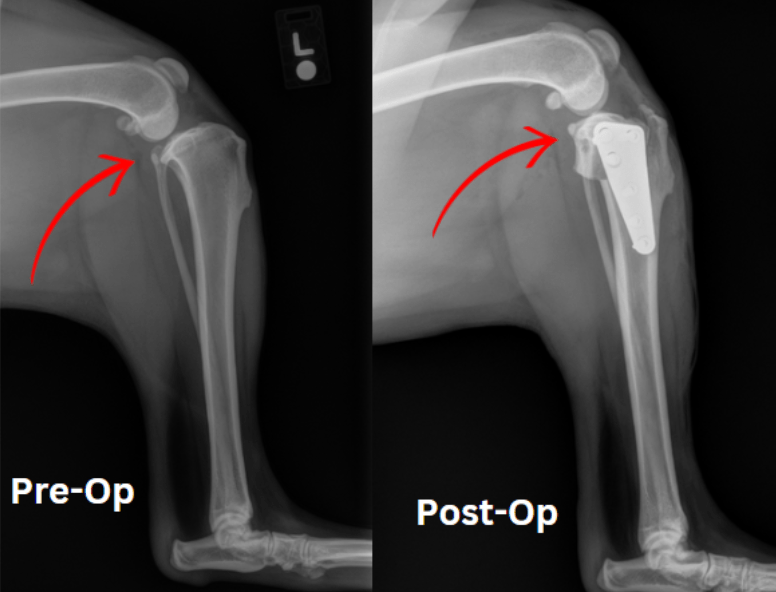

Medial Patellar Luxation Surgery (MPL) is a procedure performed to address medial patellar luxation in dogs. The goal of the surgery is to correct the misalignment of the patella, allowing it to remain in its proper position within the femoral groove.